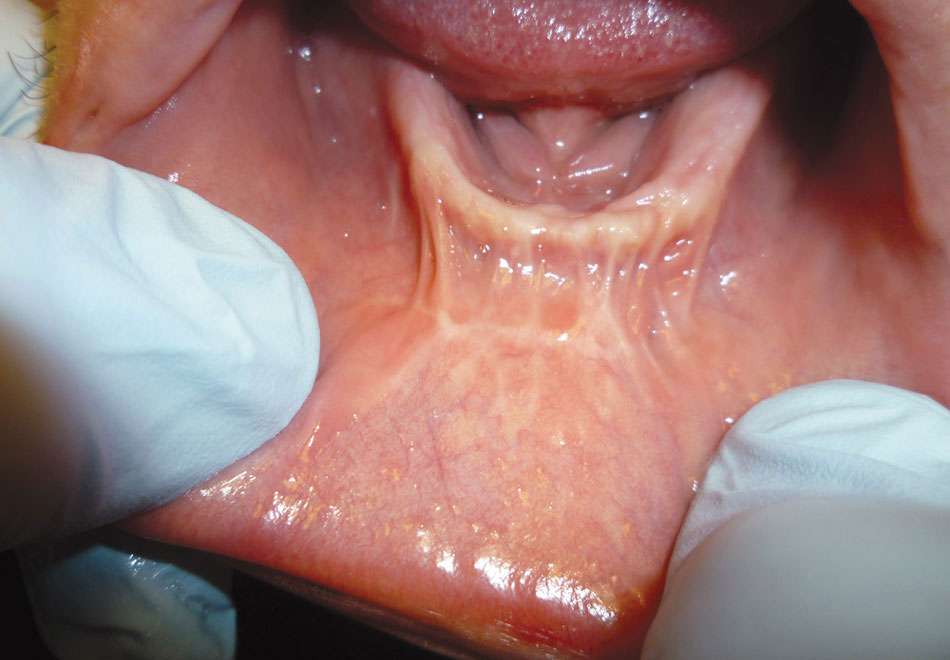

The examination revealed that the patient’s mandibular muscle attachment extended onto the crest of the ridge (Figure 6). The muscle fibers created considerable tension. Radiographic findings showed mild alveolar bone resorption as well. Such muscle placement and condition of the bone made the mandibular vestibule space inadequate for substantial denture foundation and inhibited fabrication of a complete denture. The patient’s bilateral lingual tori had been previously removed, which provided adequate vestibular height on the lingual side of the mandibular ridge. Therefore, lingual vestibular extension was not required. To take a good impression and ensure a comfortable fit with satisfactory retention and stability of the denture, it was decided to perform buccal-labial vestibular extension with the CO2 laser. The crest of the ridge and the soft-tissue condition did not require any grafting.

The clinician pulled the lower lip outward to maintain tension and facilitate soft-tissue incision. A horizontal CO2 laser incision was made starting at the left second premolar area and continued along the mucogingival junction line toward the second premolar of the contralateral side. The clinician made sure to extend the incision to the level of, but not through, the periosteum (Figure 7). Importantly, the trajectory of the incision was parallel to the bone surface. The small penetration depth of the CO2 laser wavelength enabled the clinician to remove very thin layers of tissue without collateral thermal changes or mechanical trauma to the adjacent lateral and underlying tissues. Severing thicker muscle fibers required multiple laser passes rather than a single incision.